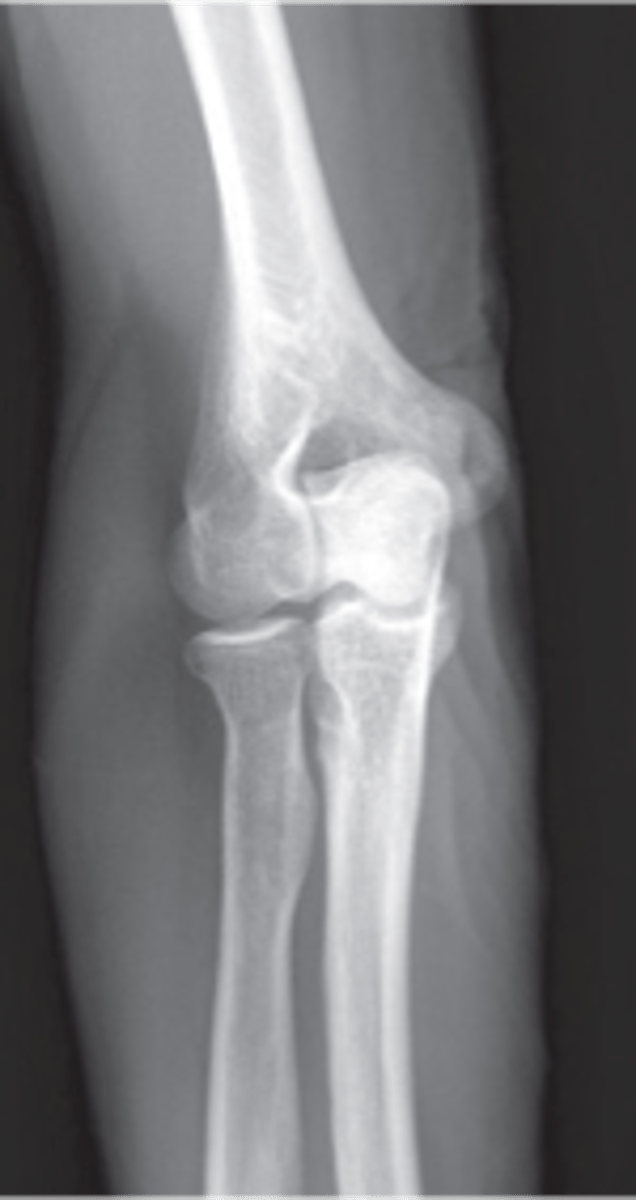

AP Elbow

AP elbow humerus parallel

AP elbow forearm parallel